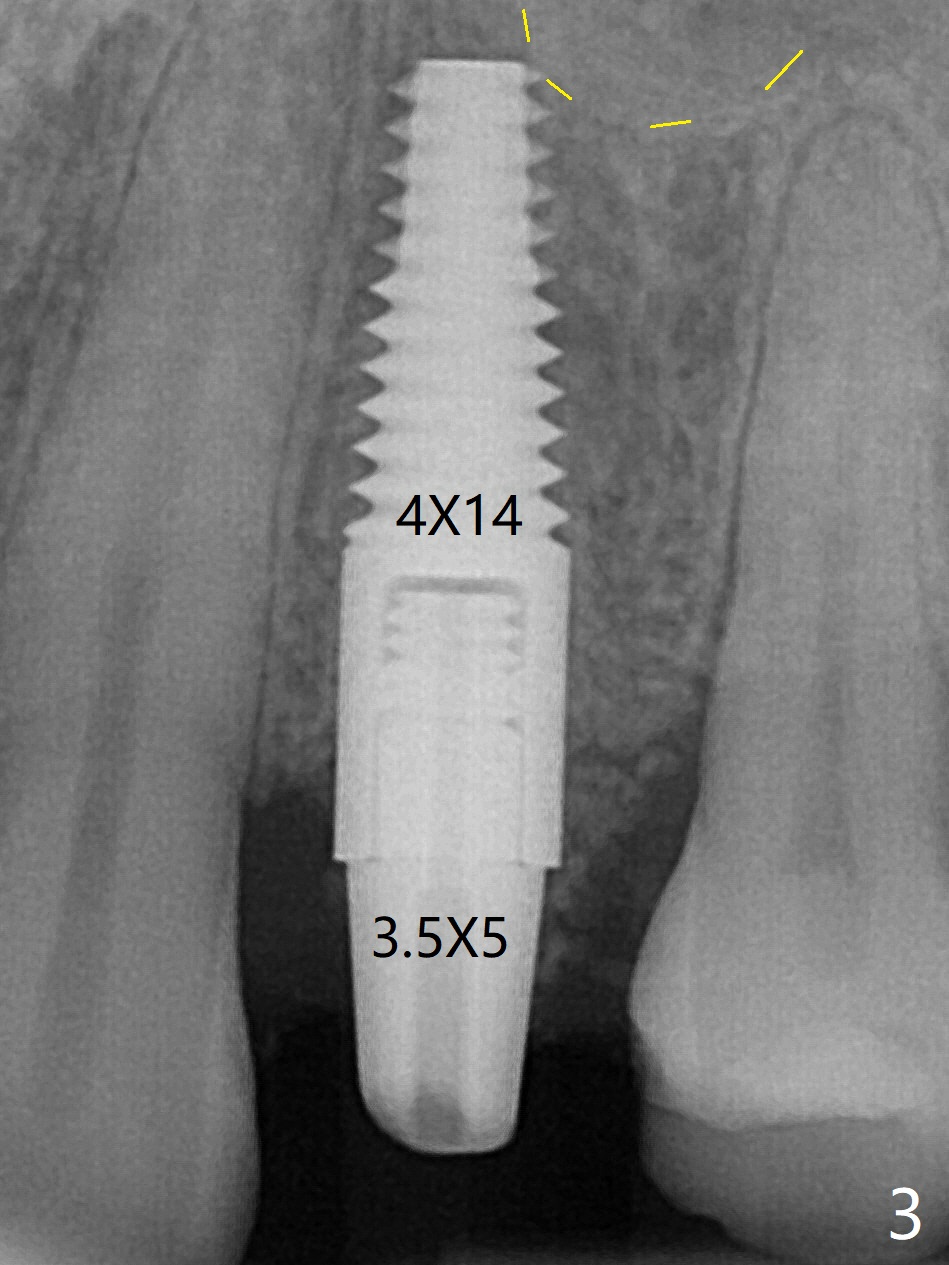

拔牙前发现患牙颊侧牙龈退缩(图一),需要软组织移植吗?拔牙后,在根尖用1,1.5,2.0 和3.0毫米骨凿打穿窦底,然后输入粘性骨粉(图四:*)。腭侧骨壁建立钻洞(有利于颊侧牙龈再生),忘了拍摄先锋钻根尖片,直接植入4x14毫米软组织水平报废植体,接近尖牙牙根(图二(黄虚线:窦底))。木已成舟,无法改变方向,又没有更长植体,只好植入同样大小植体(图三),即刻放置基台,固定骨粉和PRF膜,后者促进颊侧退缩牙龈再生,最后使用树脂敷料封闭伤口。